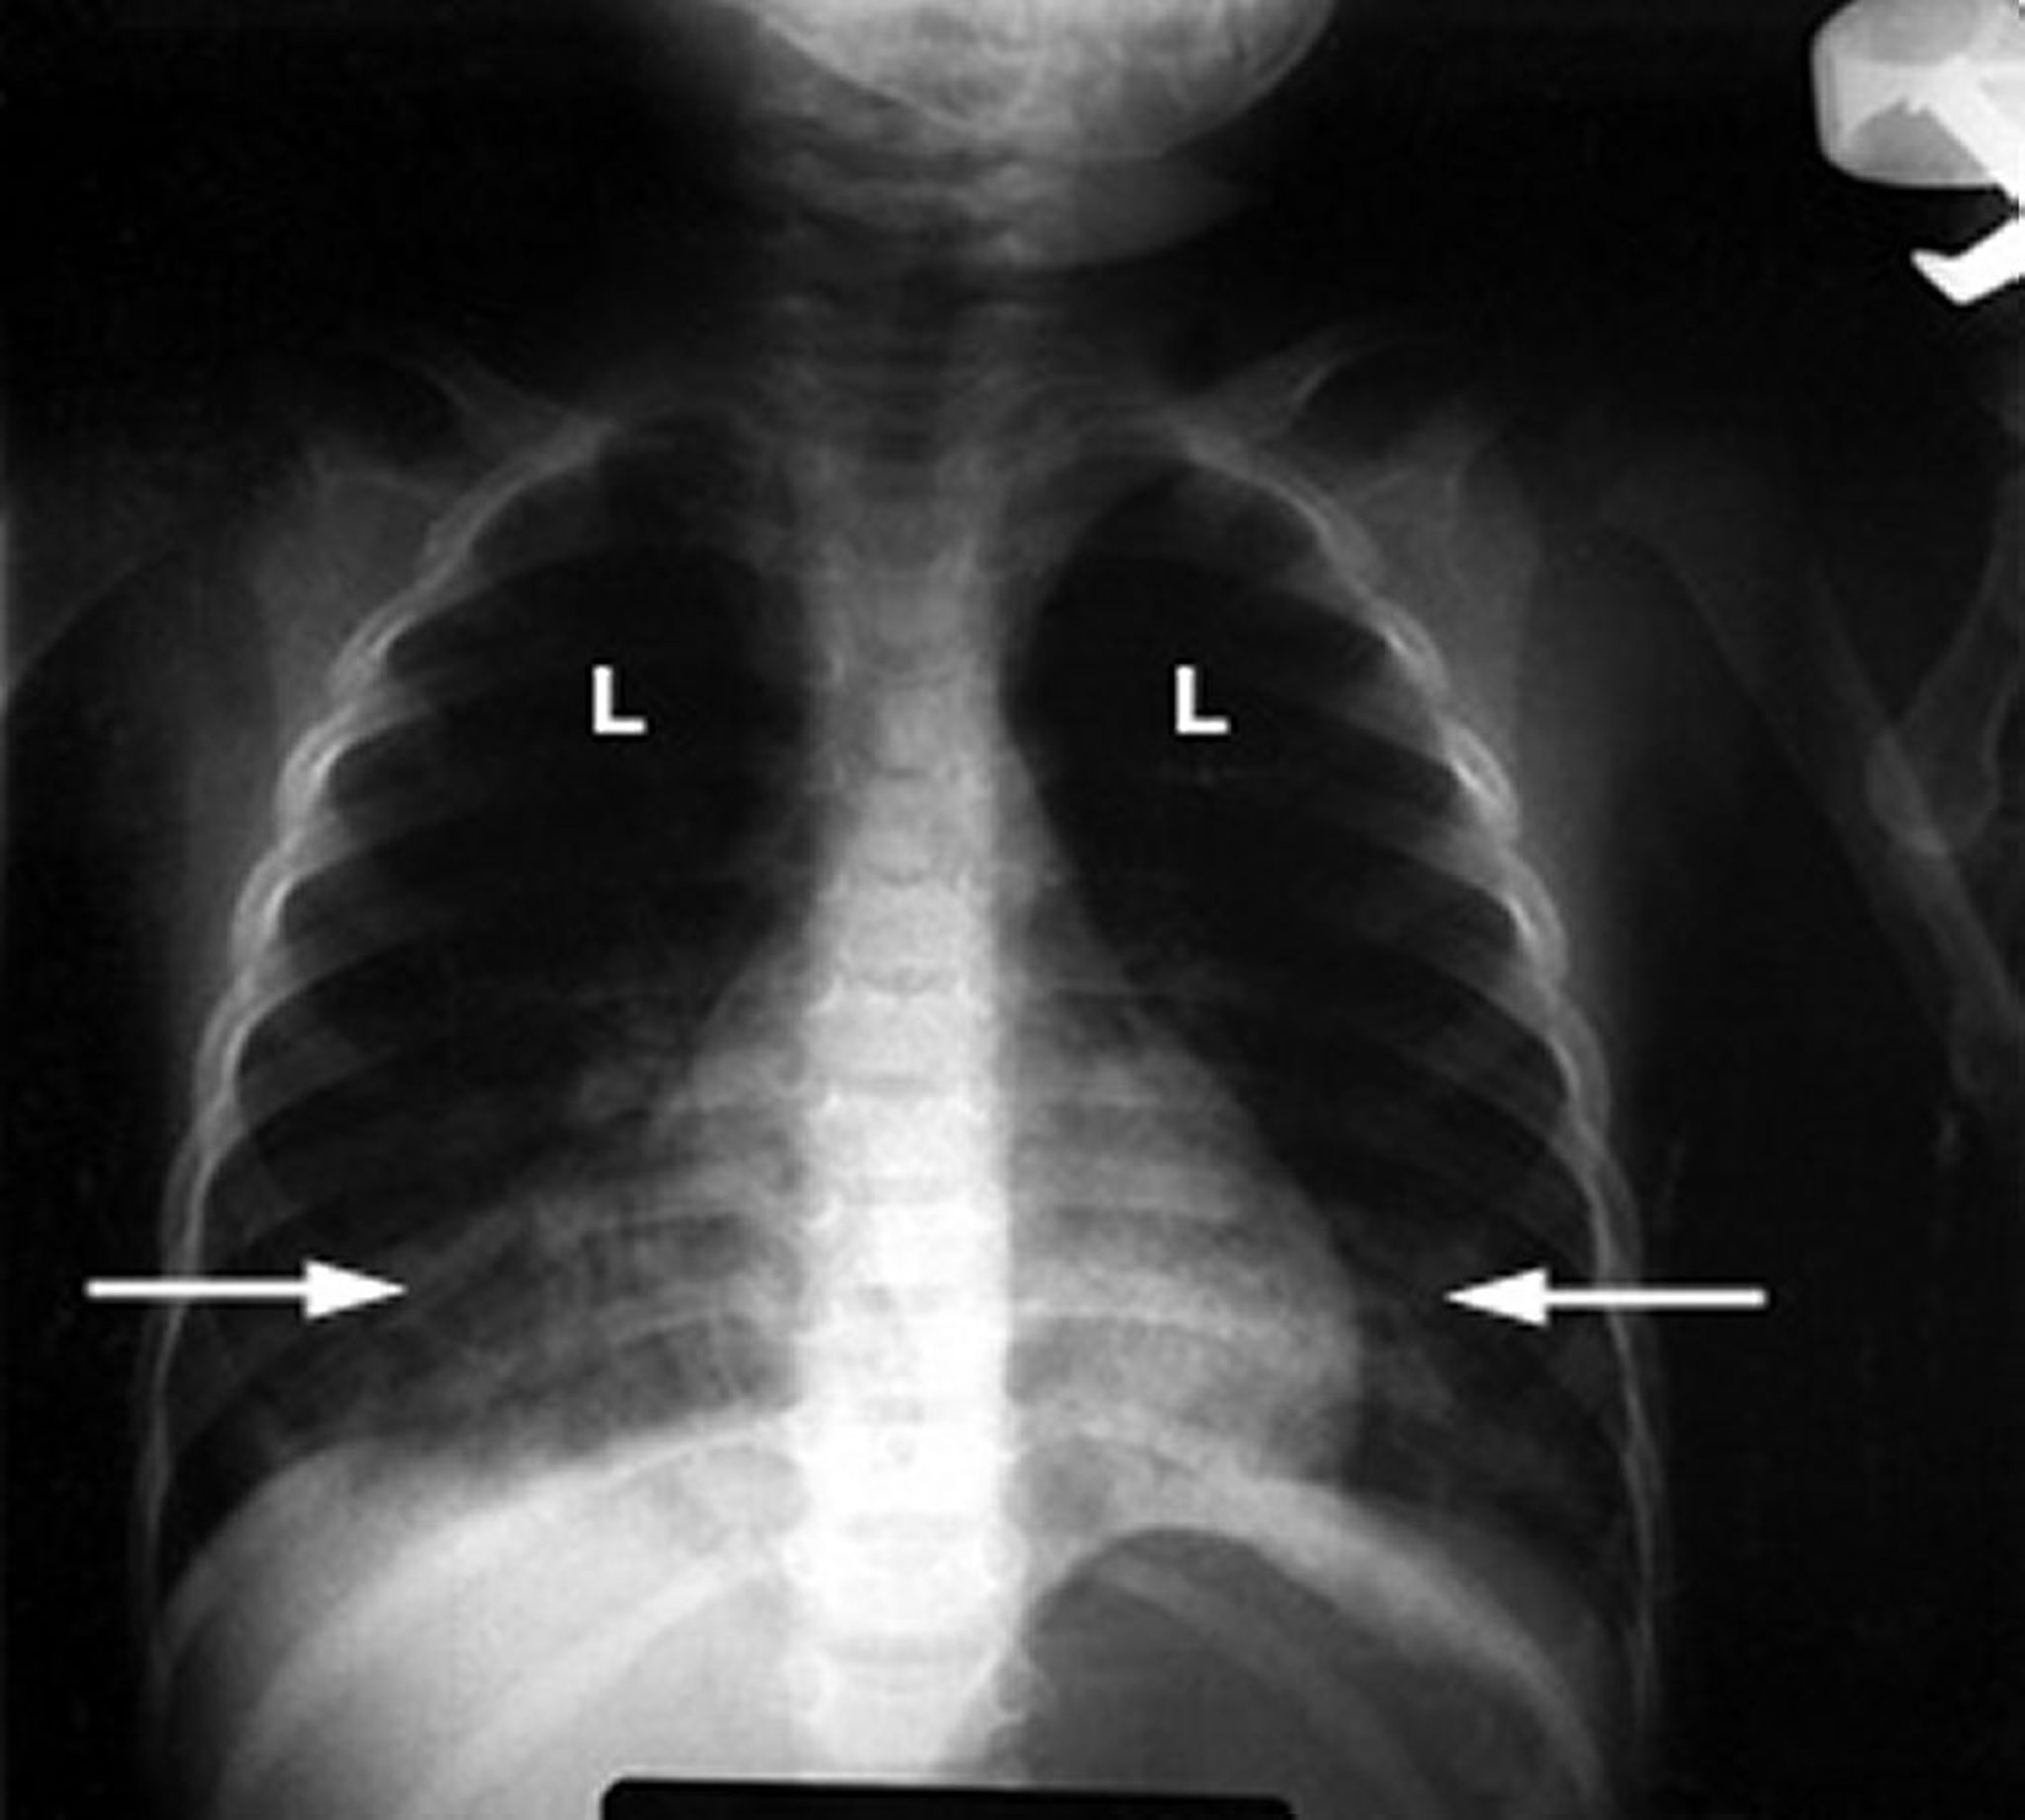

炭化水素の吸入による化学性肺炎

これは乳児の胸部X線画像で、白い綿状の浸潤影(矢印)が肺(L)に写っており、炎症が示唆されます。炭化水素中毒による肺の損傷に典型的な所見です。

Courtesy of G.Schmidt, MD.